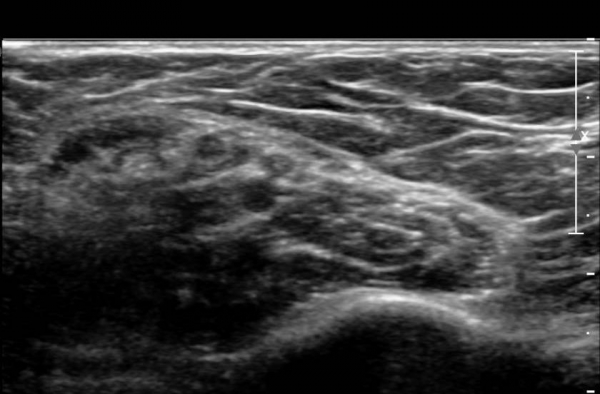

ŽÃËÀÚ¸¦ »ó¹ÚºÎ ¸»´ÜÀ¸·Î  ¿Å°Ü ÆÈ²ÞÄ¡ ºÎÅÍ ±ÙÀ§ºÎ·Î À̵¿ Çϸ鼭 Á¤Á߽Űæ Ⱦ´Ü¸é°Ë»ç¸¦

½ÃÇàÇÏ¿´´Ù(»çÁø 2).  ÆÈ²ÞÄ¡ ÁÖ¸§  ¾à  3cm ±ÙÀ§ºÎ¿¡¼­ Á¤Á߽ŰæÀÇ ÀϺΠ´Ù¹ß(fascicle)ÀÇ Àú¿¡ÄÚ ºÎÁ¾ÀÌ

°üÂûµÈ´Ù(»çÁø 3 , 4,  5,).

Á¤Á߽Űæ Á¾´Ü¸é °Ë»ç¿¡¼­µµ  Á¤Áß ½Å°æ ÀϺΠ´Ù¹ßÀÇ ¹æÃßÇü Àú¿¡Ä¿ ºÎÁ¾ÀÌ °üÂûµÈ´Ù(»çÁø 6, 7).